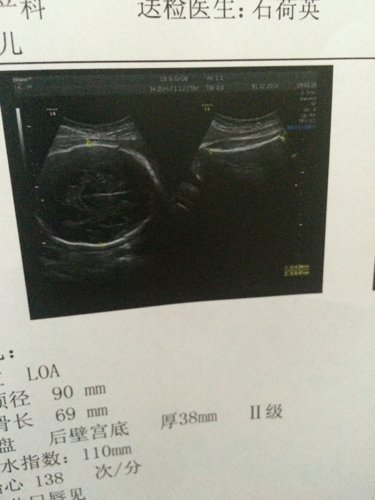

医生说羊水偏少,宝宝脚长,并且脑袋也挺大的,主要肾盂分离大到11mm 哟决定很不放心 希望懂的医生 医生说羊水偏少,宝宝脚长,并且脑袋也挺大的,主要肾盂分离大到11mm哟决定很不放心。希望懂的医生给我点建议吧! 点击展开 匿名用户 2014-12-31 09:25 为您推荐: 其他回答 你好,如果孕期的时候洋水偏少的话 ,平时的时候宝妈最好多喝点水,这样有助于增强洋水的,平时按时去医院复查 mhs÷ 2014-12-31 10:00 相关问题 胎儿37周多6天,右肾肾盂分离11mm 羊水75mm 要紧吗?我该怎么办? 胎儿超声测试值:双顶径26mm,腹径25mmX24mm,股骨长11mm,最大羊水暗区30mm,能看 12孕检结果,有液暗区11mm,医生说有先兆流产,不知道严不严重?好害怕,希望宝宝没事!